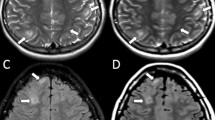

To study the MT phenomenon a three-dimensional gradient-echo sequence (TR/TE 32/8, 6° flip angle) was performed and 4 mm/2 mm overlapping sections were concurrently obtained without and with the application of a MT binomial pre-pulse (1–2–1) applied on-resonance. Images of this sequence obtained before the application of the MT pre-pulse had proton-density contrast due to the short TE and the small flip angle (Fig. 1). The MT sequence performed in the axial plane (parallel to the intercommisural line, i.e. the anterior commissure to posterior commissure line or AC–PC line) and coronal plane (perpendicular to the AC–PC line) were part of our standard protocol. Images obtained after the application of the MT pre-pulse depict structures of high MTR with low signal intensity and those of low MTR with higher intensity (Fig. 1). The duration of a complete MR examination ranged from 15 to 25 min. All MR examinations were evaluated by a paediatric neuroradiologist (M.I.A.) who was aware of each subject’s clinical condition. Brain lesions were evaluated on T2-W unenhanced and contrast-enhanced T1-W images. Based on conventional MR findings, the signal intensity of the subependymal nodules, white-matter lesions, cortical tubers, NAWM, cortex, putamina, caudate nuclei and thalami were evaluated using the region-of-interest (ROI) method. Signal intensity measurements were also performed in the control group in the cortex, putamina, caudate nuclei, thalami and frontal and occipital white matter. The ROIs were circular with a minimum size of 0.5 mm2. The MTR was calculated as:

A 17-month-old boy. a Axial proton-density MRI before the application of the MT pre-pulse shows subependymal nodules with intermediate signal intensity (arrows). b After the application of the MT pre-pulse the subependymal nodules (arrows) are of low signal intensity (high MTR) while the CSF has high signal intensity (very low MTR)